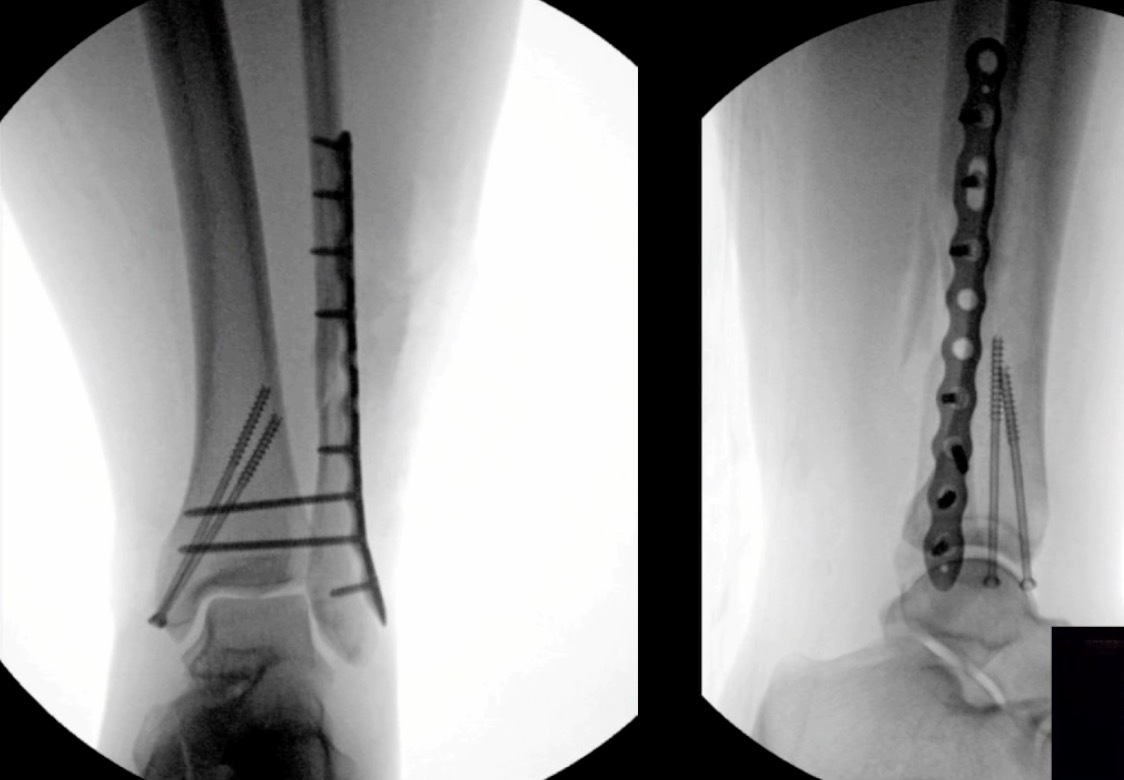

There’s much controversy in terms of should we wait or should we allow acute weight bearing following fixation of an unstable ankle fracture. Traditionally, patients were kept non-weightbearing for 6-12 weeks in some kind of cast or a boot. Nowadays, more contemporary approach is to allow earlier mobilization and protected weight bearing. Additionally, there’s many differences between North American and European schools of thought. When I give this talk to Europeans, they say “yeah we start immediate weight bearing all the time, that’s the standard.” But it’s certainly not the view in North America. I still see patients that have a beautiful x-ray with everything fixed and they’re kept in a cast for two months, which potentially defeats the whole point of surgical fixation. The benefit of surgery is to allow early mobilization and protected weight bearing. This practice can accelerate your patient’s return to work and return to life. However, nobody wants to see this x-ray in their clinic, especially with the staples still in (Figure 3).

This example is the fear that drives behavior amongst most orthopaedic surgeons who do not allow patients to move early.